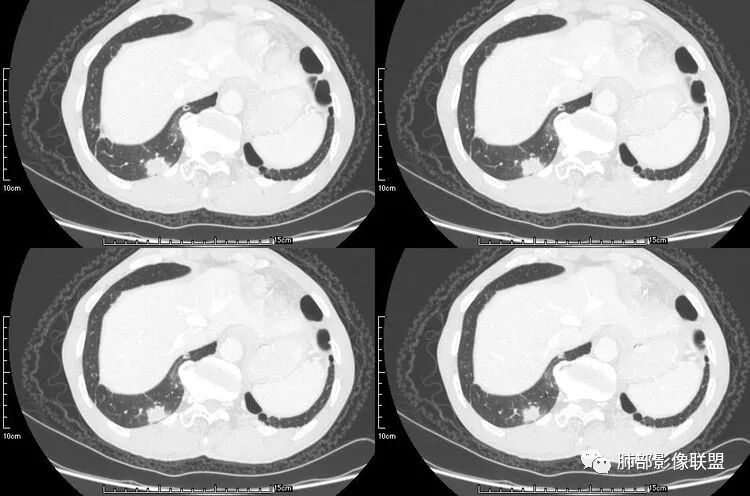

患者老年男性,咳嗽、咳痰、痰中带血伴胸闷2月余。长期大量吸烟史。查肝肾功能、血糖、血脂、心肌酶、电解质、血沉、C反应蛋白、抗“O”、类风湿因子、抗核抗体谱无明显异常。肿瘤标志物提示NSE、CYFRA21-1稍升高。胸部CT:肺气肿背景,左肺下叶后基底段不规则肿块影,见支气管截断,内见大片状低密度区及部分血管影,增强轻度强化,远端空洞形成。双肺多发不规则实性结节影、见毛刺、胸膜牵拉及血管集束,结节内见空洞形成,部分可见血管影,多位于胸膜下。双肺见多发肺大泡。综合考虑左下肺恶性病变并双肺转移。鳞癌或淋巴瘤可能。鉴别血管炎性病变及真菌感染。

本病例左肺下叶肿块,有深分叶、毛刺、胸膜牵拉凹陷、支气管截断及纵隔内淋巴结肿大等征象,都均支持病灶为恶性,如腺癌,而且叶间裂的多发结节也提示是腺癌来源可能大;双肺多发结节、肿块,大部分病灶有分叶、毛刺及胸膜凹陷的恶性征象,与原发肿瘤本身的性质有关,所以应该与左肺下叶肿块同源,而且双肺多发病灶内空洞也具有多样性;

此病例中空洞形态多样,内壁不光整,有分隔影,周围未见明显卫星灶及钙化灶,结核不太符合;患者病史慢性病史,无明显发热,缺乏中毒临床表现,急性感染基本排除;各种中性粒细胞胞浆抗体阴性,没有鼻窦炎,肾脏等病史,基本排除血管炎;霉菌性空洞常见于免疫机能低下者, 常为空洞、肺炎、伴“ 晕圈”征的结节及支气管扩张合并存在。